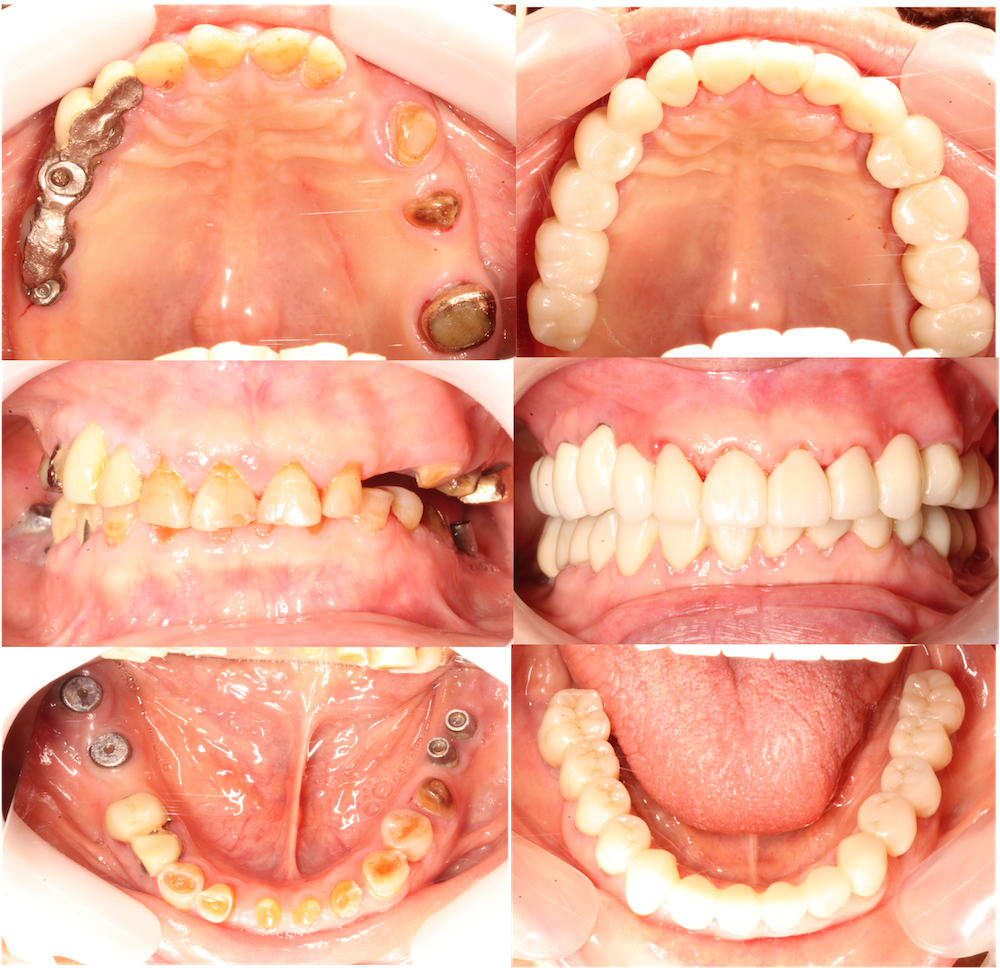

術前・術後の口腔内写真

上下奥歯にインプラント埋入し補綴されていましたが、何回も脱離や破折を繰り返し、来院時は奥歯が無い状態でした。原因は、咬合力が強いのと、奥歯が無いことで噛み合わせの位置がずれていました。

今回、ご高齢であるので、インプラントの再手術は行わずに、既存のインプラントを利用し噛み合わせを再構築(咬合再構成)することにしました。まず、奥歯のに仮歯を入れて、下がってしまった噛み合わせを上げて戻します。また、全ての歯を再形成し、仮歯を入れさせていただきました。新しい噛み合わせで、約2ヶ月過ごしていただいて、不快症状がないことを確認して、口腔内スキャナーで型取りを行いました。

噛み合わせが強いので、ジルコニアのブリッジ、クラウンを装着しました。

奥歯でなんでも噛めるようになり、また見た目も綺麗になりましたので、大変喜んでいただけました。